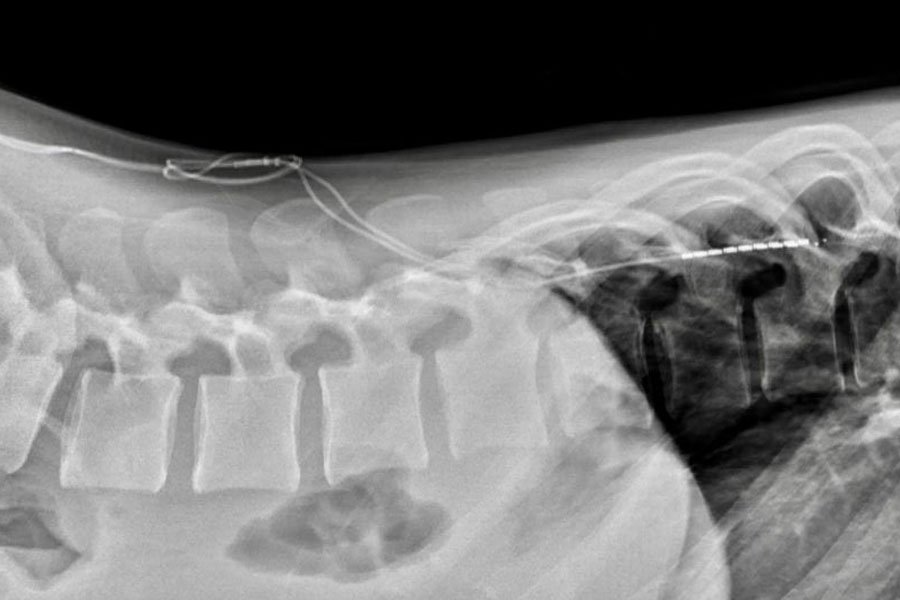

La Neurostimolazione Midollare o Spinal Cord Stimulation permette, attraverso sistemi impiantabili sotto cute costituiti da uno o più elettrodi e da un generatore d’impulsi (pacemaker), di creare un campo elettromagnetico attorno al midollo spinale, in grado di modulare la conduzione del dolore cronico.

Gli elettrodi vengono posizionati a livello dello spazio epidurale attraverso un’incisione percutanea in anestesia locale, quindi, collegati al generatore di impulsi che viene posizionato dentro una tasca sottocutanea in regione sovraglutea.

• Nella seconda fase, una volta appurata la sua efficacia antalgica a distanza di qualche settimana, il generatore viene impiantato in maniera definitiva in sede sottocutanea.